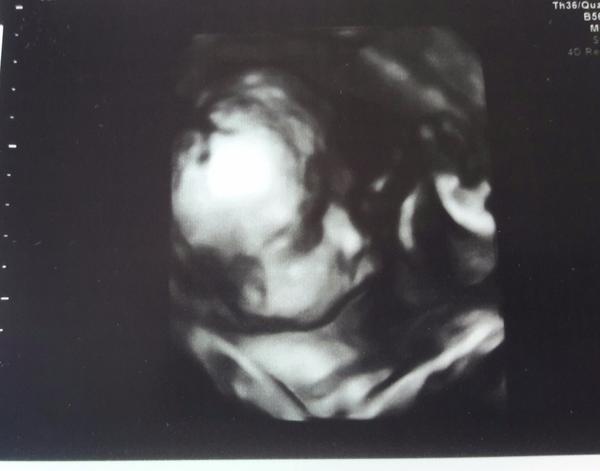

@sasenka04 ta je krasnucka babika...Som rada, ze je vsetko o.k. a verim, ze sa este otoci, treba jej navecer svietit silnou baterkou dole u Teba na brusku, mozno sa otoci za svetlom...Znie to ako blbina, no ked som cakala prveho syna a chodila som na stretnutia ohladom vsetkeho, co sa tyka babätiek, ohladom porodu, kojenia atd, tak tam sa toto riesilo, ze co robit, ak dieta je KP a jeden par, co tam boli to tam prezentovali, zevraj svietili baterkou a babätko sa im takto otocilo do polohy hlavickou dole 😉...No poskusaj, co sa da, snad sa princezna este otoci...Drzim palceky 🙂